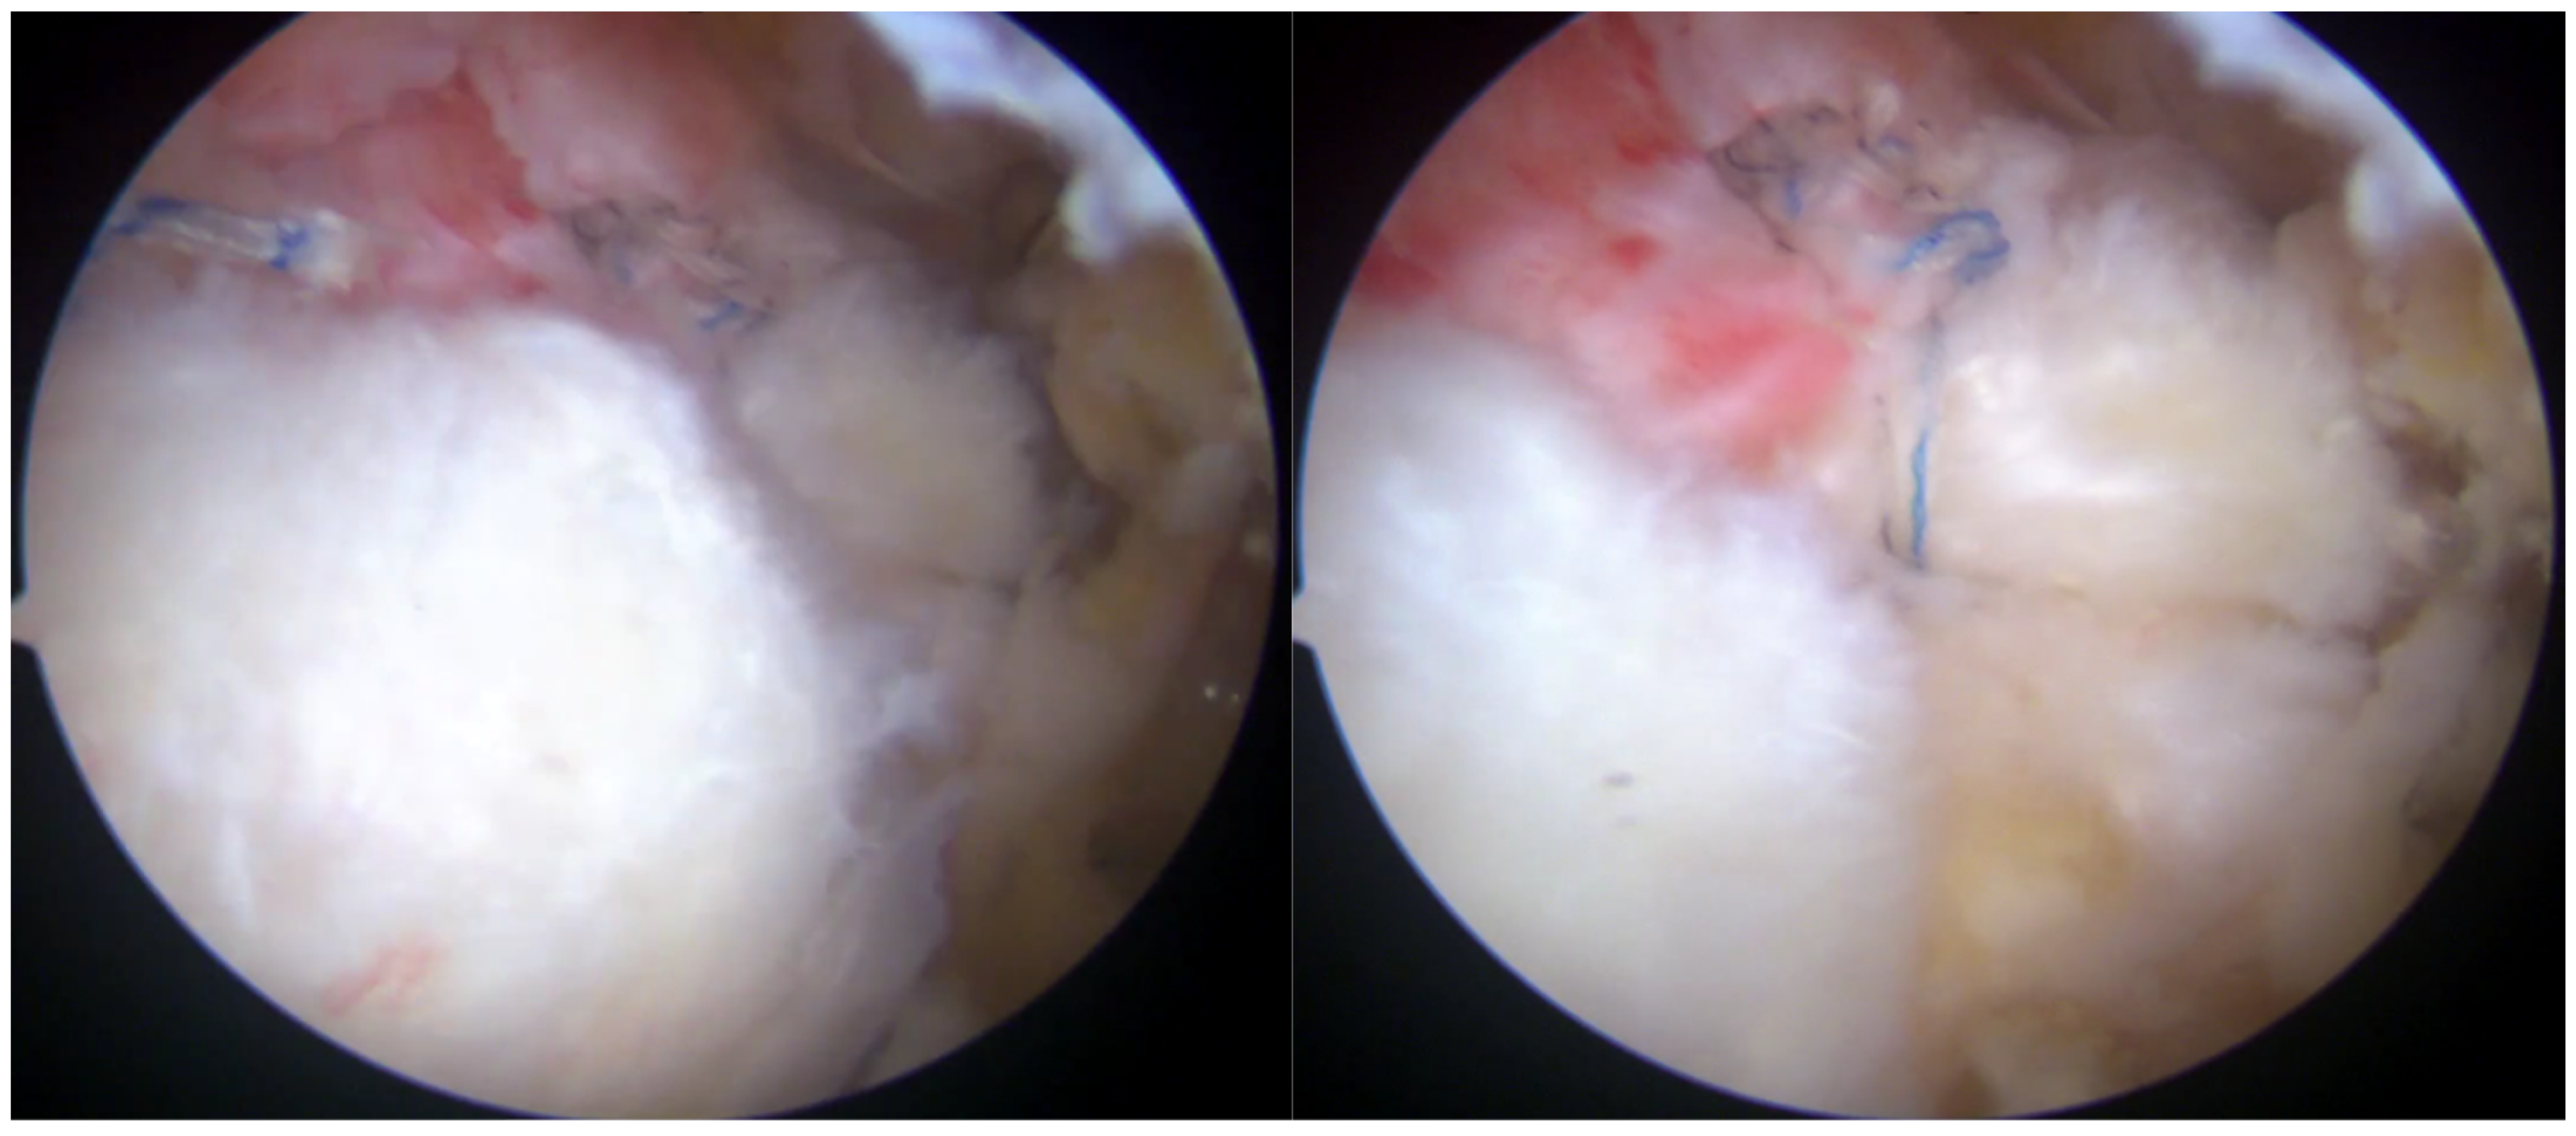

Post-repair arthroscopic visualization revealed a partial repair of the supraspinatus tendon, leaving a noticeable gap in the rotator cuff tissue (Figure 5).

Figure 5.

Rotator cuff repair has been achieved with two suture anchors, but a defect remained due to the absence of sheet 2 of the supraspinatus tendon.

To address this residual defect, a bioinductive collagen membrane (Regeneten, Smith and Nephew) was implanted to augment the repair and enhance healing. The Regeneten patch is available in two sizes, with the appropriate size selected based on the tear’s dimensions and morphology. The bursal surface of the patch is distinctively marked to differentiate it from the interlaced articular surface.

A thorough bursectomy was performed to create adequate space for patch augmentation. Soft tissue lateral to the tendon insertion was ablated to ensure direct contact between the lateral edge of the implant and the bone. The patch was loaded onto an arthroscopic delivery device and introduced into the subacromial space via a lateral cannula. After achieving the desired medial-to-lateral positioning over the repair construct, the delivery device was engaged, allowing the implant to unfurl. Two additional accessory portals were created for optimal anchor placement. Anchors were deployed with precision, using a quick motion to secure the implant to the tendon construct. Eight tendon anchors were inserted to affix the patch securely along its edges, ensuring stabilization (Figure 6). Although bone anchors could be used to enhance the contact between the lateral portion of the implant and the bone, they are not commonly utilized by the senior Author.

Figure 6.

The bioinductive implant (Regeneten) was positioned carefully over the repaired tendon site. The implant served as a scaffold to encourage the growth of new tendon-like tissue and enhance the strength of the repair.

The stability and positioning of the implant were confirmed with a probe. Following the verification of the repair, all instruments were removed, and the surgical wounds were closed in the standard fashion.